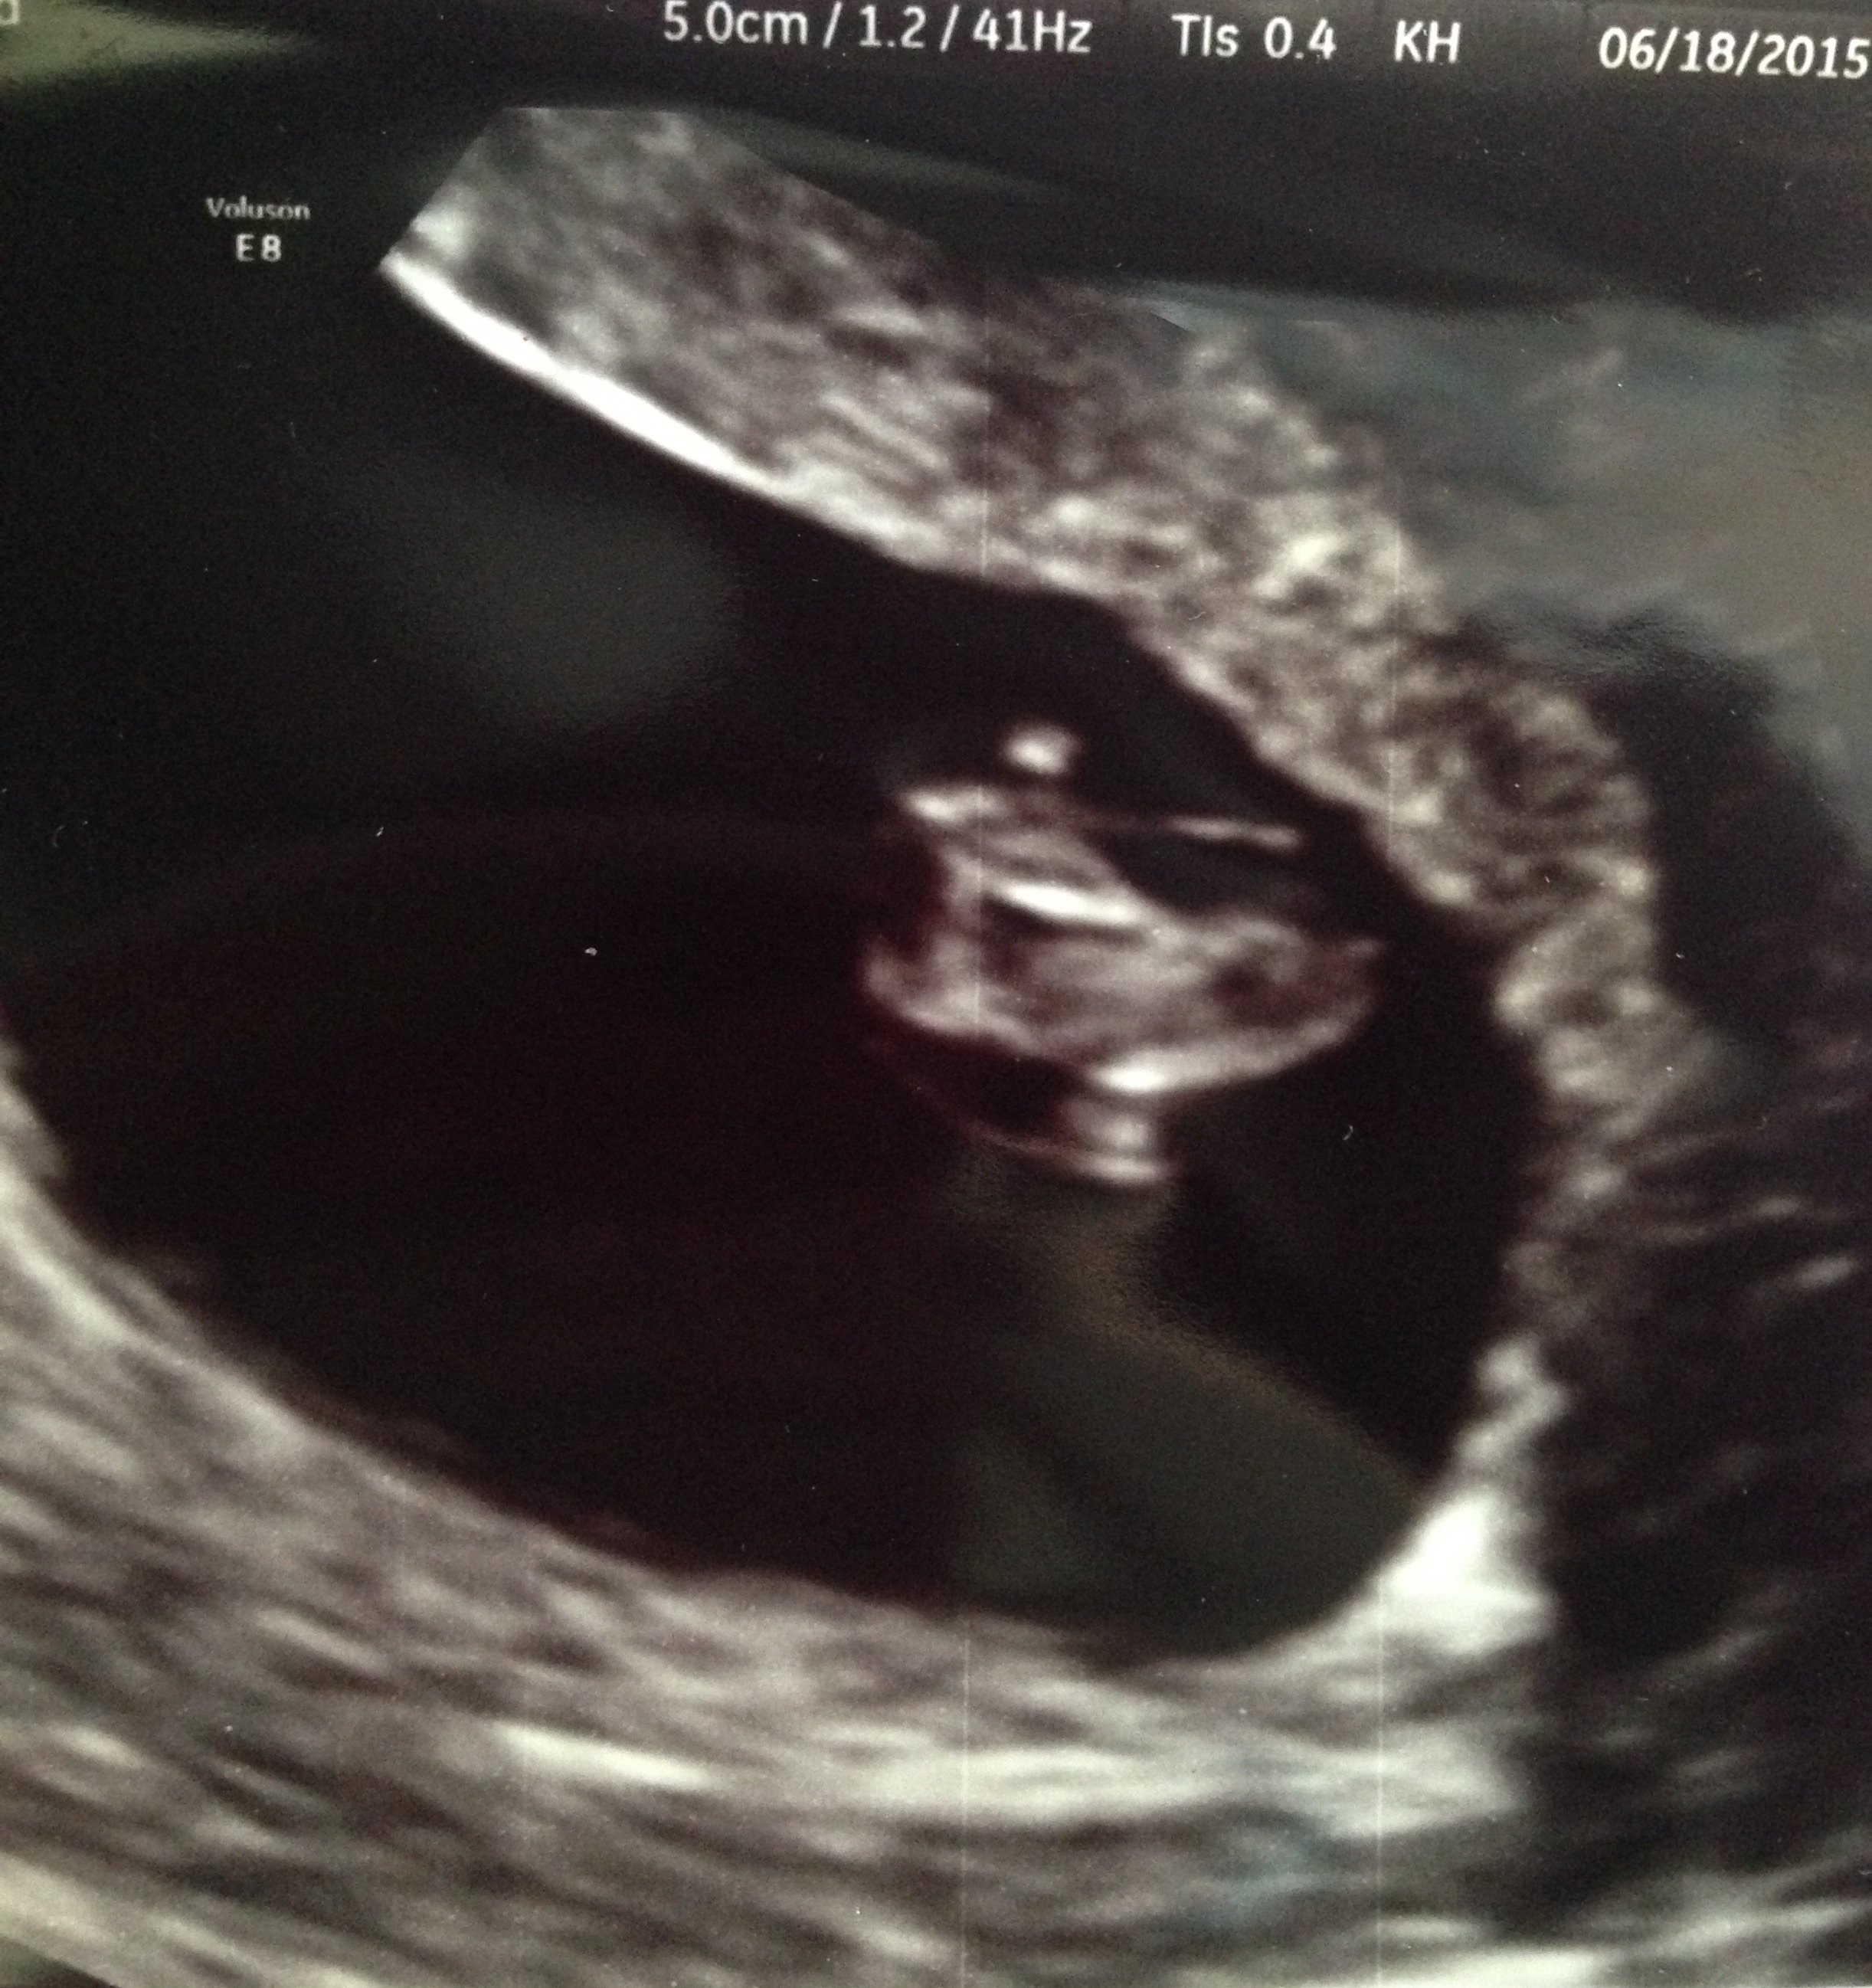

Is it just me, or do you see a litle human form in there to

ETA: HR 130